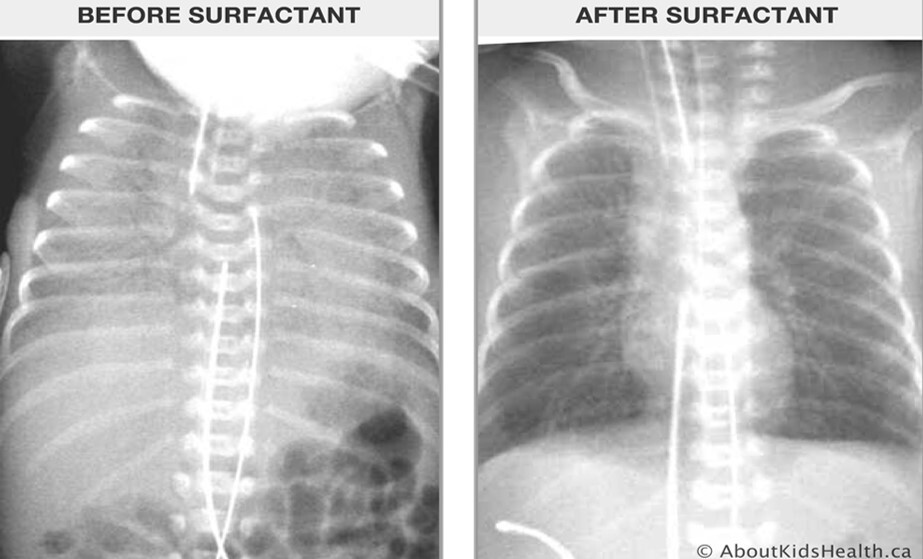

What’s the treatment of the following condition?

Surfactant

Neonatal respiratory distress syndrome/ hyaline membrane disease

: Neonate is presented with nasal flaring and grunting. This is due to surfactant deficiency, therefore need cortisol secretion (need to hit baby and starts crying, release of cortisol increased 🡪 Type II pneumocytes are responsible for secreting surfactant

Neonatal Respiratory Distress Syndrome / Hyaline Membrane Disease